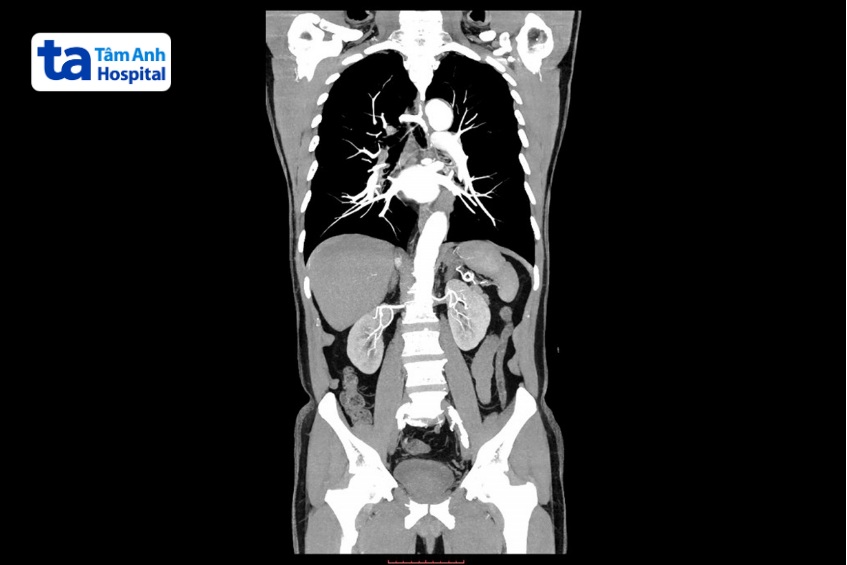

Chụp CT ngực bụng chậu (Computed Tomography, còn gọi là chụp cắt lớp vi tính) là kỹ thuật chẩn đoán hình ảnh sử dụng tia X để tạo ra các hình ảnh lát cắt của khu vực ngực bụng chậu như lồng ngực, hệ thống sinh sản, tiêu hóa, nội tiết và tiết niệu. Qua đó, bác sĩ có thể quan sát cấu trúc chi tiết bên trong vùng ngực bụng chậu, phát hiện những bất thường nếu có.

CT ngực bụng chậu có khả năng cung cấp hình ảnh với độ phân giải và tương phản tốt, giúp phát hiện những bất thường nhỏ như sỏi thận cho đến các bệnh lý nghiêm trọng như ung thư. Đây là một trong những phương pháp chẩn đoán hình ảnh hiệu quả, cung cấp hình ảnh nhanh, chính xác

Ngoài ra, trung tâm còn đầu tư hệ thống máy móc, trang thiết bị hiện đại như hệ thống chụp CT 768 lát cắt Somatom Drive (Siemens, Đức), hệ thống chụp CT 1975 lát cắt, máy công nghệ hiện đại nhất của hãng GE HealthCare (Mỹ). Các máy CT hiện đại này mang đến hình ảnh chất lượng cao, tốc độ quét nhanh chóng, tính linh hoạt trong ứng dụng lâm sàng… cho phép bác sĩ quan sát các cấu trúc chi tiết, phát hiện những tổn thương nhỏ ở vùng ngực bụng chậu, từ đó đưa ra chẩn đoán chính xác, giúp xây dựng phác đồ điều trị phù hợp với từng đối tượng.